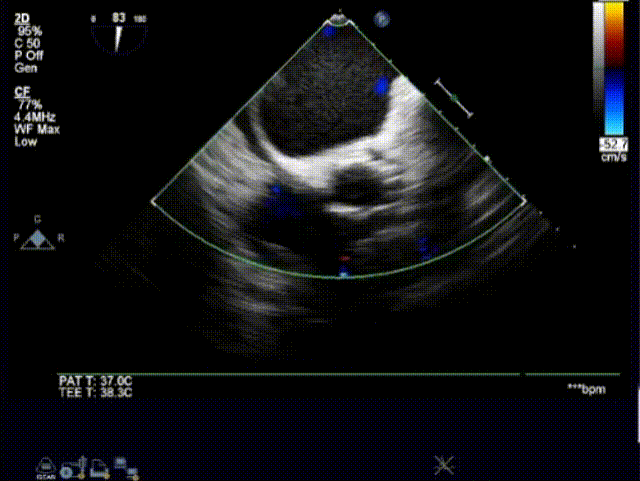

超声下评估植入深度

植入后超声评估: